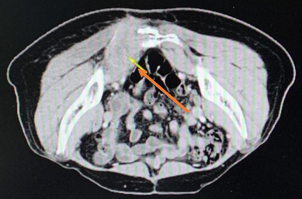

2019年10月12日CT:

1.14cm

7.66*4.54

2019年12月14日CT:

1.5*1.1

7.9*5.1

转移灶评估:两肺较前稍增大、骶骨肿块较前增大

病情评估:PD

PFS:8.9个月